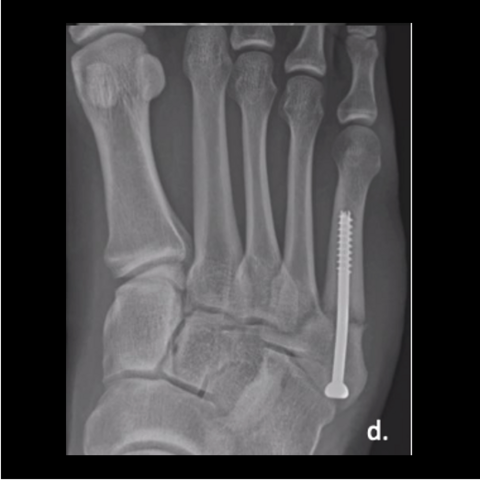

Figure 4d

Figure 4d. The 24-year-old soldier jumped off the back of a truck, refracturing his metatarsal. Here is the foot a year post-surgery after jumping off the truck.